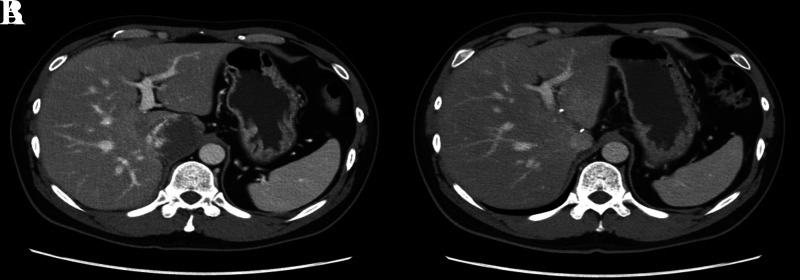

Results: The first patient, with a 6.8-cm hemangioma, underwent Spiegel lobectomy with the Xi system in 157 minutes and was discharged on day 3 without complications. The second patient, with a 2.5-cm hepatocellular carcinoma, underwent complete caudate lobectomy using the Xi system and was discharged on day 5. The last patient, with a 3-cm cystic lesion, underwent Spiegel lobectomy with the SP system and was discharged on day 6.